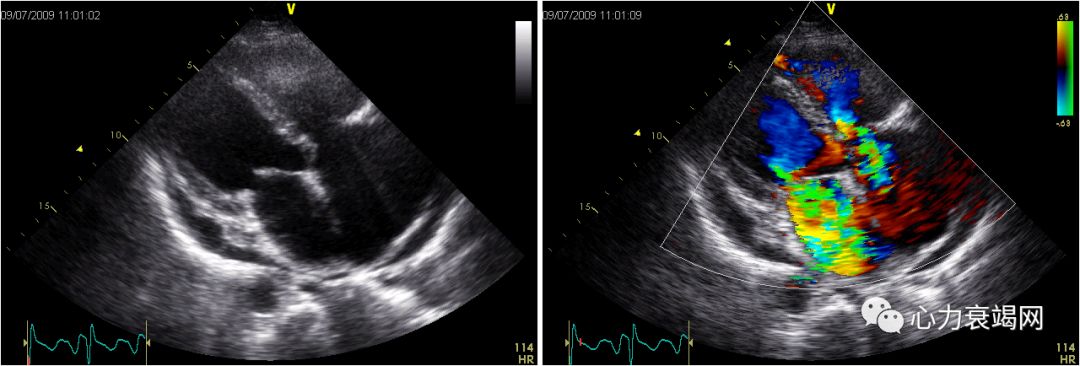

超声心动图:双平面法LVEF48%,左心室心尖部、后壁中下部运动减弱,心尖部变薄)。左心室增大。轻度二尖瓣关闭不全,左冠状动脉7.5mm, 右冠状动脉8mm

三支病变